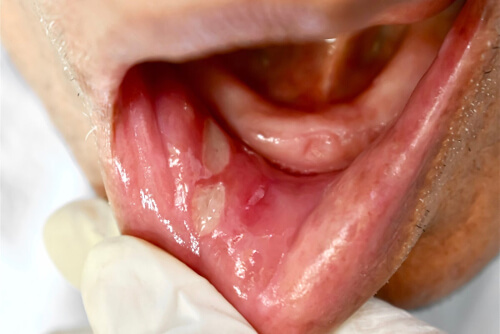

Urazy te są często bolesne, więc takie czynności, jak mycie zębów, jedzenie, picie lub mówienie, mogą powodować pewien dyskomfort. Owrzodzenia w jamie ustnej objawiają się zwykle jako białawy owal z czerwonym obszarem wokół niego.

Drobne owrzodzenia mają średnicę mniejszą niż 10 milimetrów i są najczęściej występująca postacią. Są płytkie i znajdują się na krawędziach języka lub wewnętrznej śluzówce warg lub policzków.

Powodują intensywny ból promieniujący na sąsiednie obszary, ale najczęściej ustępują same w ciągu mniej niż tygodnia. Pojawiają się wiele razy w różnych odstępach czasowych.